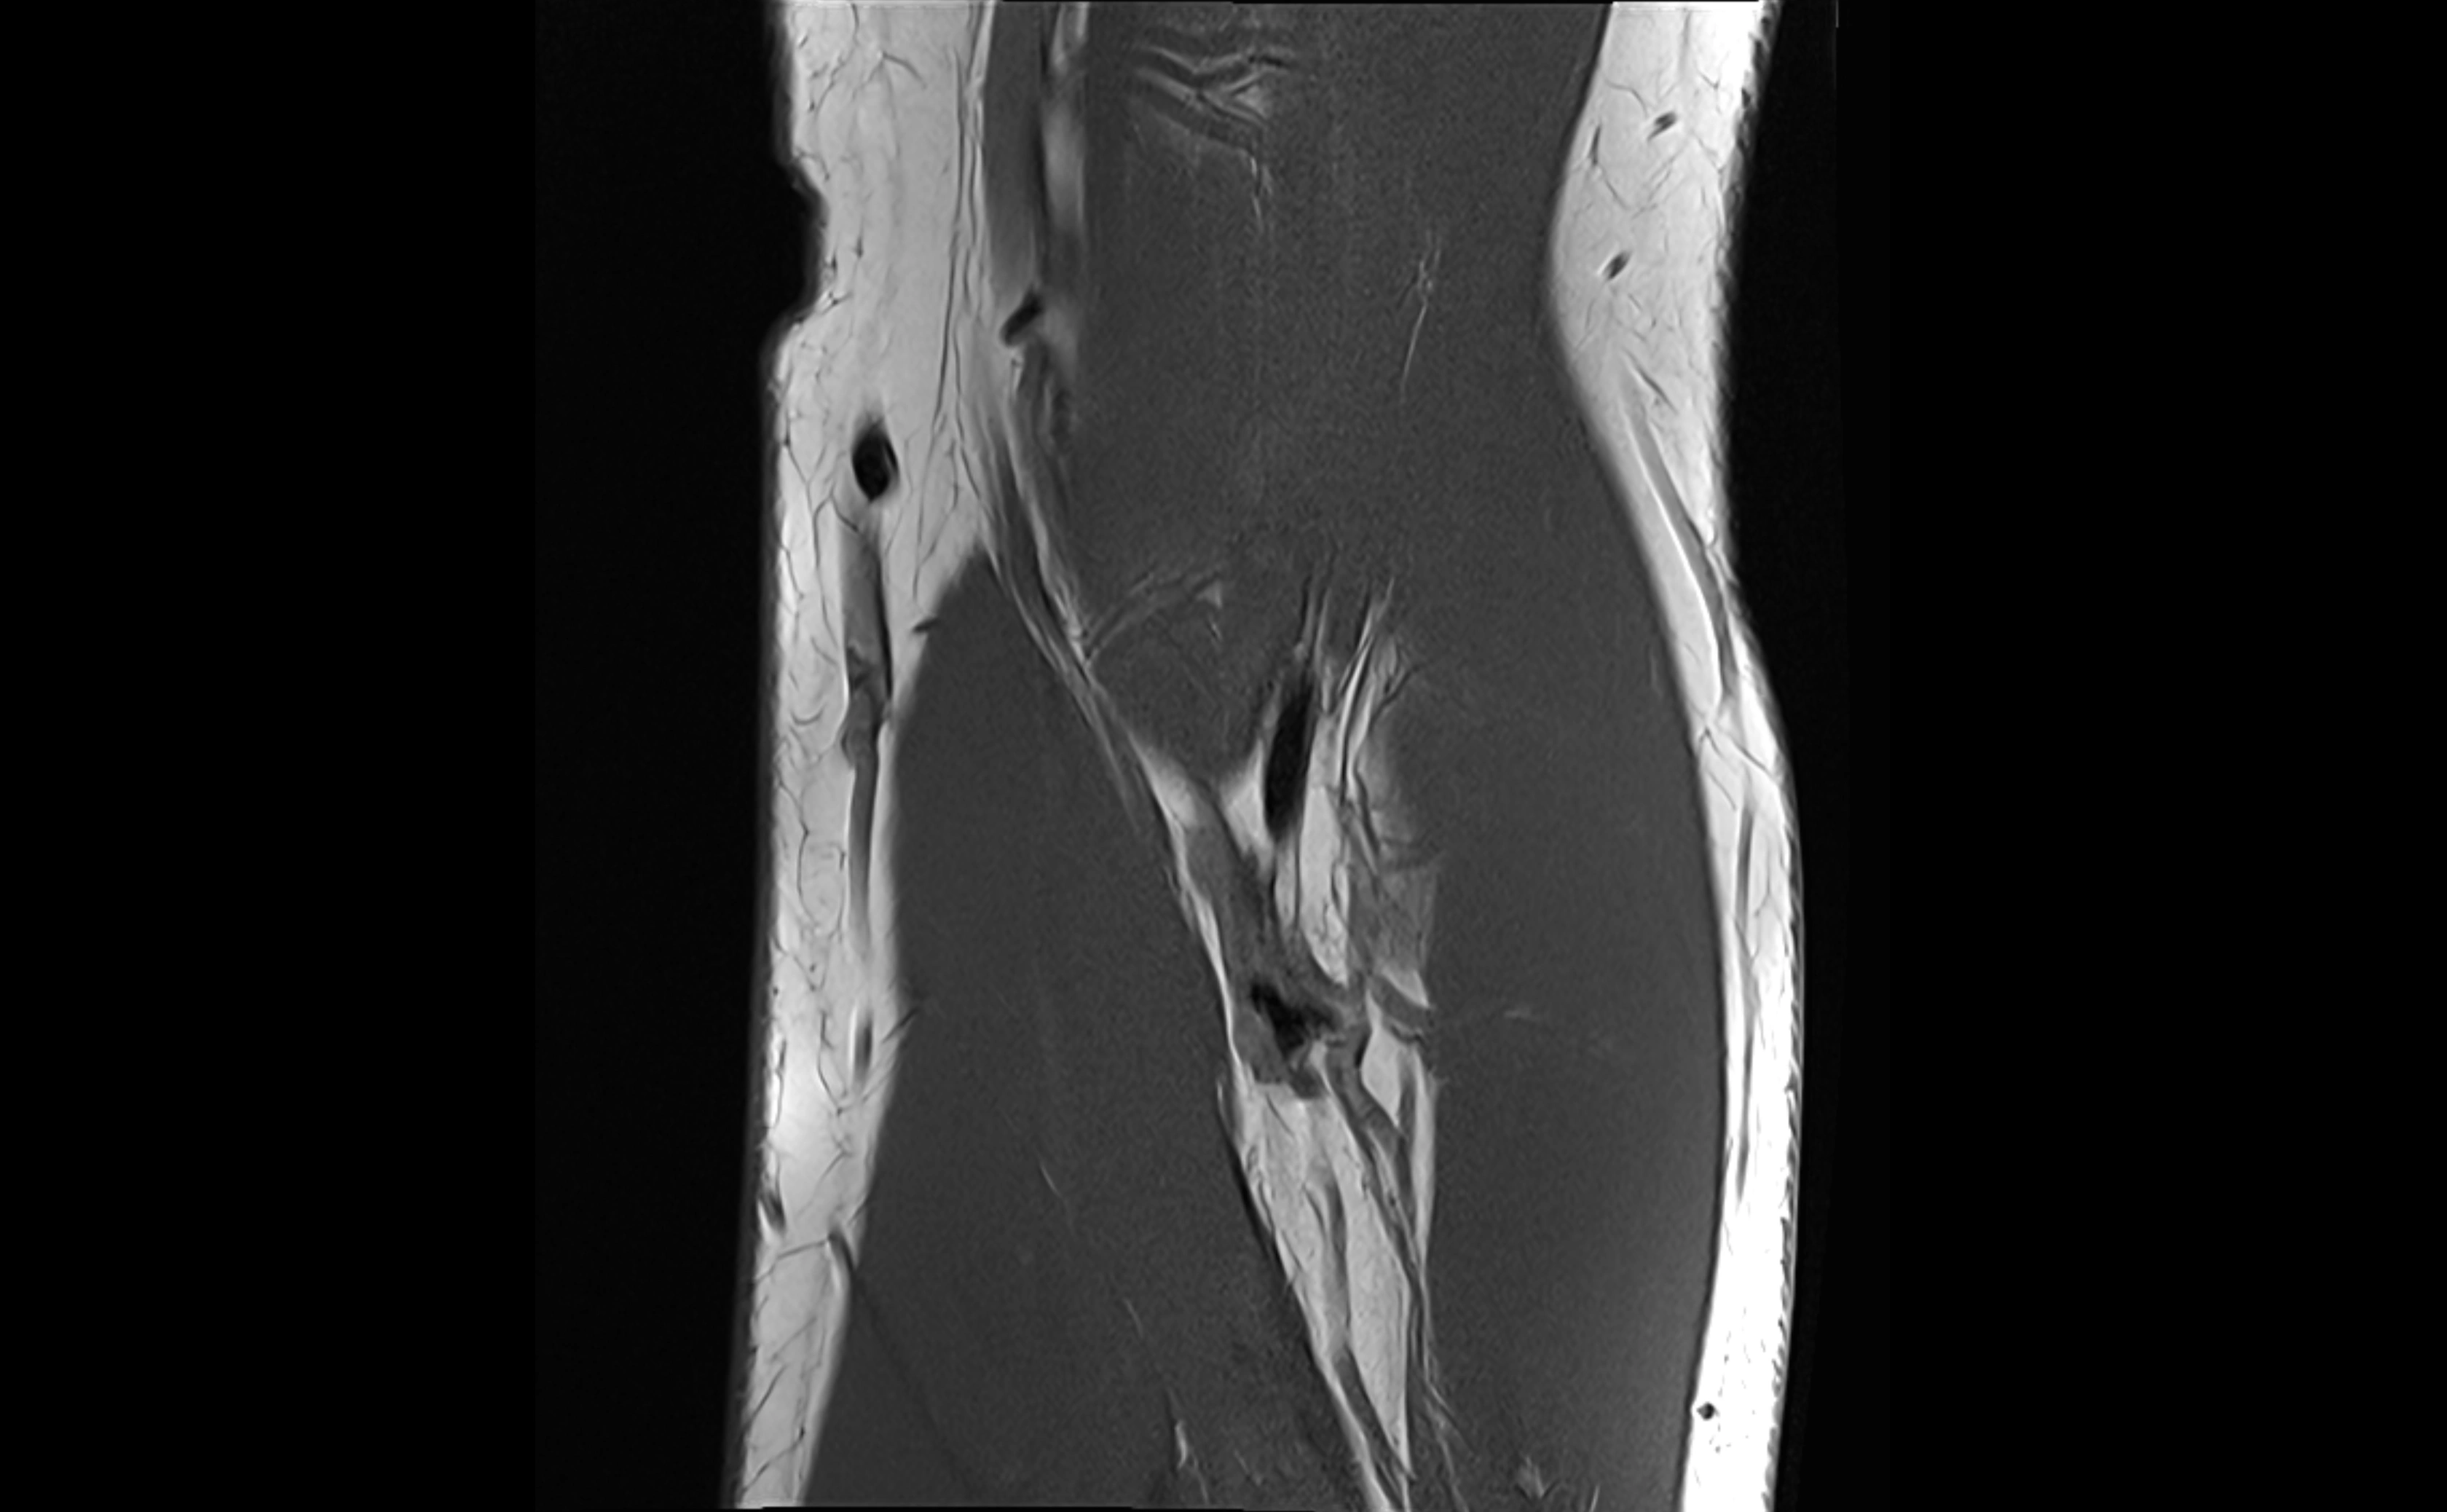

MRI images

image